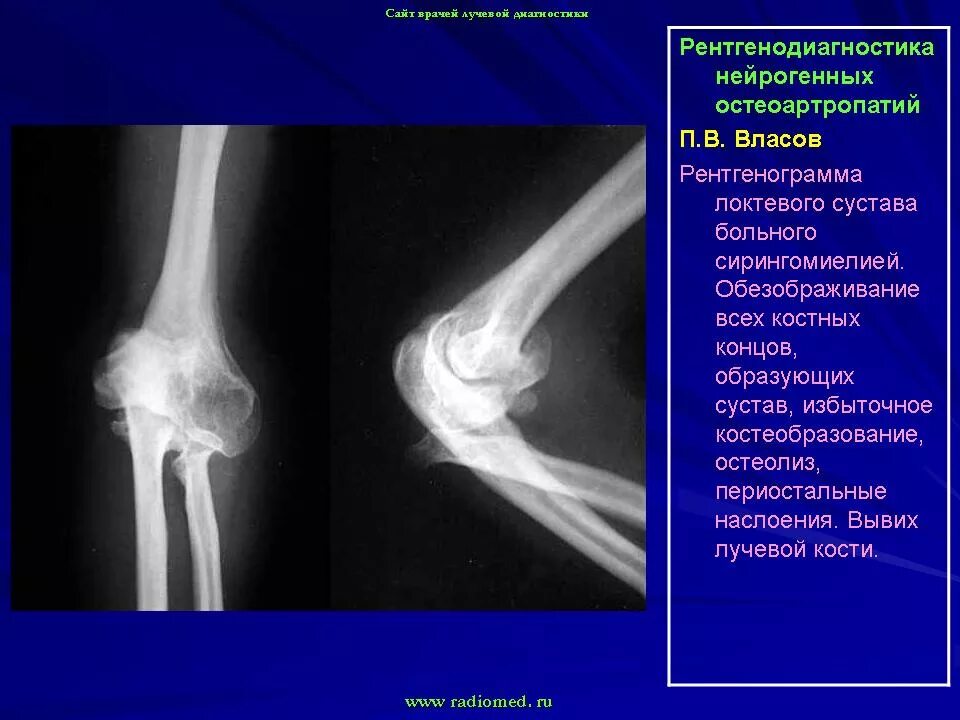

Локтевой сустав инвалидность